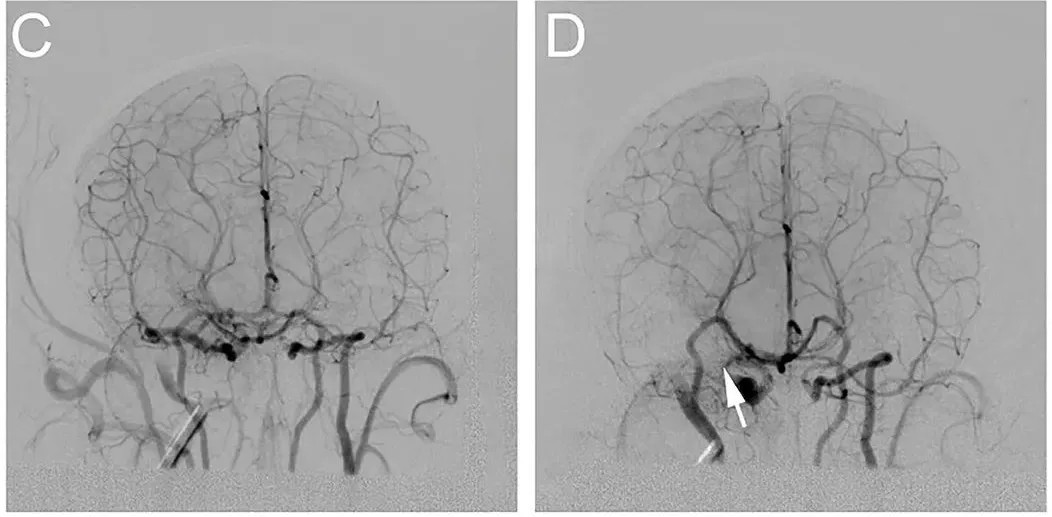

浦灵生物的MCAO(Middle Cerebral Artery Occlusion,大脑中动脉闭塞)模型是模拟缺血性中风的有效动物模型。通过精确控制闭塞部位和时间,该模型精确再现了人类中风的病理过程,为研究中风机制和潜在治疗方案提供了重要工具。   DSA脑血流成像和实时大脑中动脉栓塞中风影像。

目前,浦灵生物已建立的成熟食蟹猴MCAO模型,相关数据已发表于Frontiers in Neurology杂志,并借助该动物模型成功助推了多款新药的临床前药效评价。- 血管再通情况:使用CTA、MRA和CTP成像评估血管再通效果。

- 微创性操作:通过DSA指导下的血管插管,血栓定位准确且手术创伤小,降低了实验动物的术后并发症风险,减少手术干扰,提高实验结果的真实度。